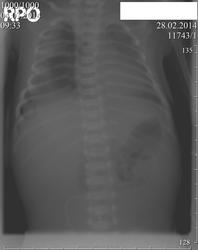

Пол пациента: Женский пол Тип патологии: Другое Область исследования: Грудная клетка и верхние дыхательные пути Методы исследования: Rg Новорождённая, 6 дней. Синдром дыхательных расстройств. https://radiomed.ru/sites/default/files/styles/case_slider_image/public/user/406/nov..2jpg.jpg?itok=Lrt5rUZE ID:36001 Ср, 05/03/2014 - 22:05 #1 Almo Не на сайте Был на сайте: 4 часа 12 минут назад Зарегистрирован: 28.09.2008 - 18:50 Публикации: 8256 Возникли вопросы по оценке субстрата тени справа в нижнем поле. Что это может быть? Приветствуются любые версии. Ср, 05/03/2014 - 22:18 #2 Андрей Юрьевич Не на сайте Был на сайте: 6 дней 4 часа назад Зарегистрирован: 16.11.2008 - 22:16 Публикации: 18098 Мой вариант - кожная складка Андрей Юрьевич Ср, 05/03/2014 - 22:26 #3 NIL Не на сайте Был на сайте: 21 час 17 минут назад Зарегистрирован: 25.11.2013 - 20:50 Публикации: 18206 А снимок сделан лёжа или вертикально? "Слушай всех, прислушивайся к немногим, решай сам".© Ср, 05/03/2014 - 22:45 #4 Almo Не на сайте Был на сайте: 4 часа 12 минут назад Зарегистрирован: 28.09.2008 - 18:50 Публикации: 8256 Снимок выполнен в положении лёжа на спине (видна трубка аппарата ИВЛ). Ср, 05/03/2014 - 22:50 #5 алкс Не на сайте Был на сайте: 10 лет 2 недели назад Зарегистрирован: 24.10.2012 - 22:55 Публикации: 2915 Андрей Юрьевич wrote: Мой вариант - кожная складка ! Только за. Ср, 05/03/2014 - 22:59 #6 Almo Не на сайте Был на сайте: 4 часа 12 минут назад Зарегистрирован: 28.09.2008 - 18:50 Публикации: 8256 Кожная складка -вариант.А не может такая скиология, быть обусловлена коллабированием лёгкого на фоне пневматоракса? Ср, 05/03/2014 - 23:04 #7 алкс Не на сайте Был на сайте: 10 лет 2 недели назад Зарегистрирован: 24.10.2012 - 22:55 Публикации: 2915 Коллапс- спадение вроде, т.е. ближе к сердцу, а тут легкое норм. размера. Ср, 05/03/2014 - 23:10 #8 NIL Не на сайте Был на сайте: 21 час 17 минут назад Зарегистрирован: 25.11.2013 - 20:50 Публикации: 18206 Снизу - да, но вверху видится какое-то треугольное затемнение.Может - придираюсь.Приложения: "Слушай всех, прислушивайся к немногим, решай сам".© Ср, 05/03/2014 - 23:20 #9 Андрей Юрьевич Не на сайте Был на сайте: 6 дней 4 часа назад Зарегистрирован: 16.11.2008 - 22:16 Публикации: 18098 Вот ссылка http://www.wikiradiography.com/page/Neonatal+Chest+Radiography смотреть Skin Folds There are multiple skin folds (white arrows) These can be misinterpreted as a pneumothorax Извините, на русском под рукой нет. Андрей Юрьевич Чт, 06/03/2014 - 07:48 #10 Gulnara Не на сайте Был на сайте: 5 лет 10 месяцев назад Зарегистрирован: 14.12.2011 - 18:54 Публикации: 168 Тень ,возможно,за счет складки на пеленке.Лучше повторить снимок.А в верхнем отделе правого легкого есть снижение пневматизации. Чт, 06/03/2014 - 08:21 #11 Almo Не на сайте Был на сайте: 4 часа 12 минут назад Зарегистрирован: 28.09.2008 - 18:50 Публикации: 8256 Это последний снимок.На первом точно был пневмоторакс. Чт, 06/03/2014 - 08:55 #12 Almo Не на сайте Был на сайте: 4 часа 12 минут назад Зарегистрирован: 28.09.2008 - 18:50 Публикации: 8256 Добавлено изображение. Чт, 06/03/2014 - 15:59 #13 Makcimalist Не на сайте Был на сайте: 11 лет 8 месяцев назад Зарегистрирован: 08.05.2010 - 14:28 Публикации: 1994 NIL wrote: Снизу - да, но вверху видится какое-то треугольное затемнение.Может - придираюсь. Придираетесь по существу. Недорасправлено лёгкое там наверху - с учётом анамнеза... Almo wrote: Это последний снимок.На первом точно был пневмоторакс. Хотя, если бы печень не помогла, решил, что снимок не отзеркален - и сердце на нём справа, а не слева... А если без анамнеза предположил бы недорасправление сегмента в результате аспирации... -------------- "Просто, по видимости, не видеть логики в очевидных вещах - это тоже одно из свойств некоторых умов, наряду с грустными думами о свойствах ума других." © Vega 08/10/2011

Возникли вопросы по оценке субстрата тени справа в нижнем поле. Что это может быть? Приветствуются любые версии.

Снимок выполнен в положении лёжа на спине (видна трубка аппарата ИВЛ).

Кожная складка -вариант.А не может такая скиология, быть обусловлена коллабированием лёгкого на фоне пневматоракса?

Коллапс- спадение вроде, т.е. ближе к сердцу, а тут легкое норм. размера.

Снизу - да, но вверху видится какое-то треугольное затемнение.Может - придираюсь.

Тень ,возможно,за счет складки на пеленке.Лучше повторить снимок.А в верхнем отделе правого легкого есть снижение пневматизации.

Это последний снимок.На первом точно был пневмоторакс.

Придираетесь по существу. Недорасправлено лёгкое там наверху - с учётом анамнеза...

А если без анамнеза предположил бы недорасправление сегмента в результате аспирации...